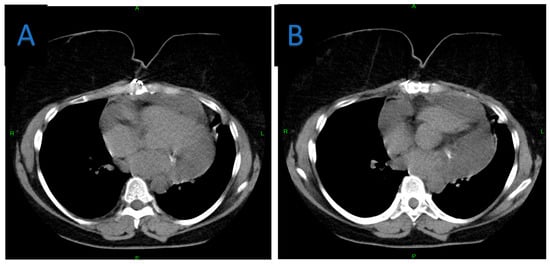

A Rare Case of Multilocular Mesothelial Inclusion Cysts of the Pericardium: Diagnosis, Treatment, Follow Up, with Comprehensive Review of the Literature

by Ali Shadmanian, Kosha Patel, Endre Alács, Henriette Gavallér, Szilva Agocs and Miklós Bitay

Background: Multilocular mesothelial inclusion cysts—also known as benign multicystic mesothelioma (BMM)—are rare, typically arising in the peritoneal cavity. Pericardial involvement is extremely uncommon and can pose diagnostic and therapeutic challenges due to their recurrent and infiltrative nature. Accurate diagnosis and surgical strategy are [...] Read more.

Background: Multilocular mesothelial inclusion cysts—also known as benign multicystic mesothelioma (BMM)—are rare, typically arising in the peritoneal cavity. Pericardial involvement is extremely uncommon and can pose diagnostic and therapeutic challenges due to their recurrent and infiltrative nature. Accurate diagnosis and surgical strategy are critical for management and recurrence prevention. Methods: We present the case of a 36-year-old woman with a prior history of malignant melanoma who developed recurrent multilocular cystic masses of the pericardium. Initial imaging with echocardiography, cardiac magnetic resonance (CMR), and computed tomography (CT) revealed multilocular pericardial cysts. Surgical resection was performed under cardiopulmonary bypass (CPB), but complete excision was limited due to epicardial infiltration. Histopathology confirmed a benign mesothelial origin. One year later, recurrence prompted a second surgical intervention with total pericardiectomy and Gore-Tex patch reconstruction. Results: Postoperative recovery was uneventful in both instances. Follow-up imaging at 6 and 12 months demonstrated no significant recurrence. Histological analysis confirmed benign cysts lined with mesothelial cells, positive for calretinin and WT-1. This represents one of the first documented living cases of pericardial BMM managed with staged surgery and total pericardiectomy. Conclusions: Pericardial BMM is a rare, benign, but potentially recurrent lesion. In cases of extensive or recurrent disease, total pericardiectomy may offer definitive treatment. Multimodal imaging, histopathological evaluation, and personalized surgical planning are essential for effective management. Full article

Figure 1